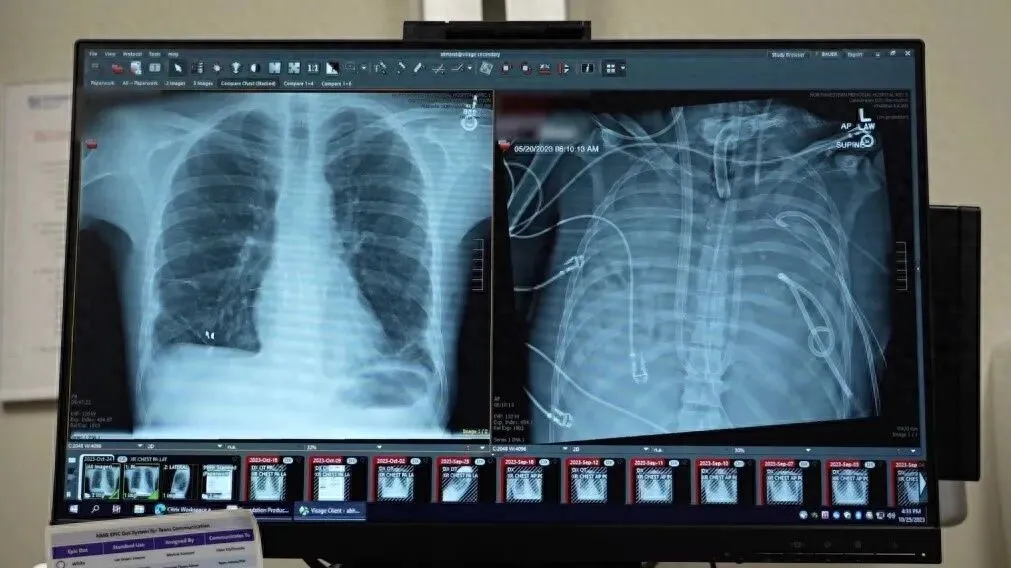

患者的新肺 (左) 与被切除的病肺(右)

肺是人类生存所不可缺少的器官。但有这样一名 33 岁的危重患者,他因严重流感引发的感染而双肺损毁,并遭遇多器官衰竭,接着切除双肺,接入特制的“人工肺”系统,最终神奇地活了 48 小时直至完成肺移植。此病例来自《细胞》(Cell)杂志子刊《医学》(Med)杂志 2026 年 3 月刊发的报告。

病肺被切除后,患者情况开始好转:血压恢复稳定,受损器官逐步修复,感染也得到控制。48 小时后,合适的供体肺出现;医生顺利完成双肺移植手术。如今两年多过去,这名患者的肺功能恢复良好,已回归正常生活。